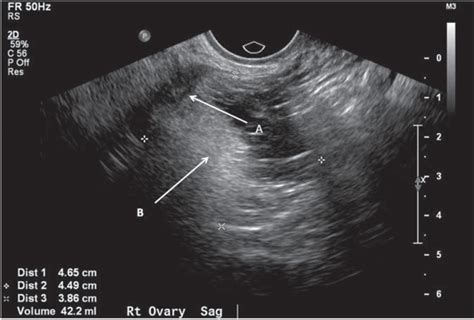

When a physician suspects a dermoid cyst ovary, they will utilize specific diagnostic tools to confirm the presence, size, and location of the mass. Imaging is the gold standard for diagnosis because the specific contents of these cysts—such as fat, calcium (teeth/bone), and fluid—have distinct appearances on scans.

Pelvic Ultrasound The primary tool to visualize the cyst and determine if it is solid or fluid-filled.